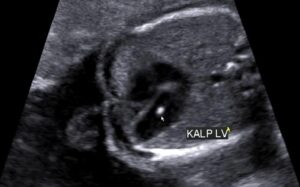

Fetal İntrakardiyak Ekojen Odak Nedir?

Kalpte ekojenik odak, ultrason ile doğum öncesi fetal anomali taramasında saptanabilen görece yaygın bir bulgudur. Kalp kapaklarının ...